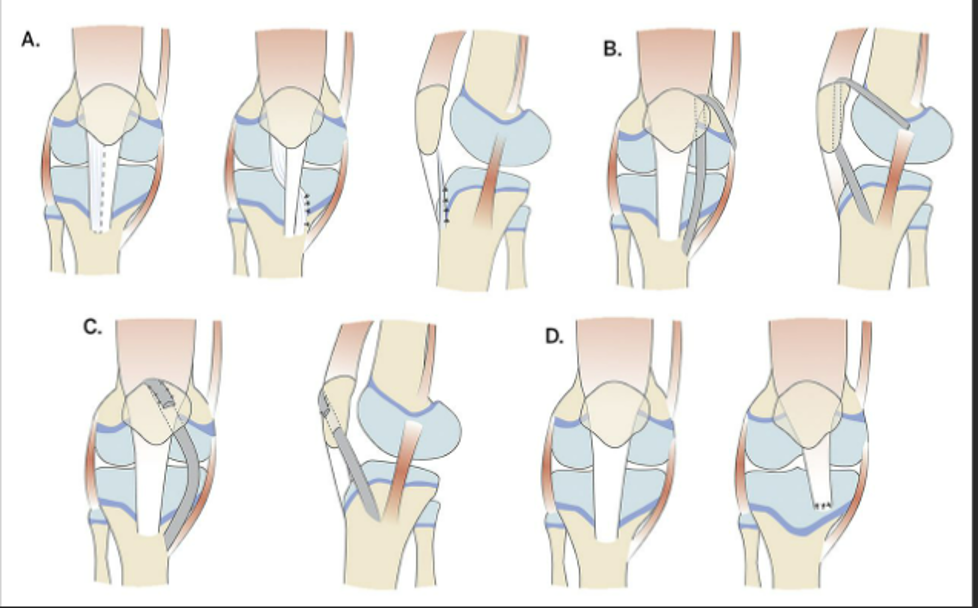

# Knee: ACL Tear Tx

Treatment: Almost always need surgical repair (unless older and inactive) - Femoral/tibial tunnel, graft fixation - Bone-Patella-Bone autograft*, quad tendon/ham autograft, allograft - Repair associated damaged structures (meniscus/MCL) ACL brace during recovery controversial Physical therapy after surgery Pearls: Often associated with MCL or medial meniscus injury (50%)